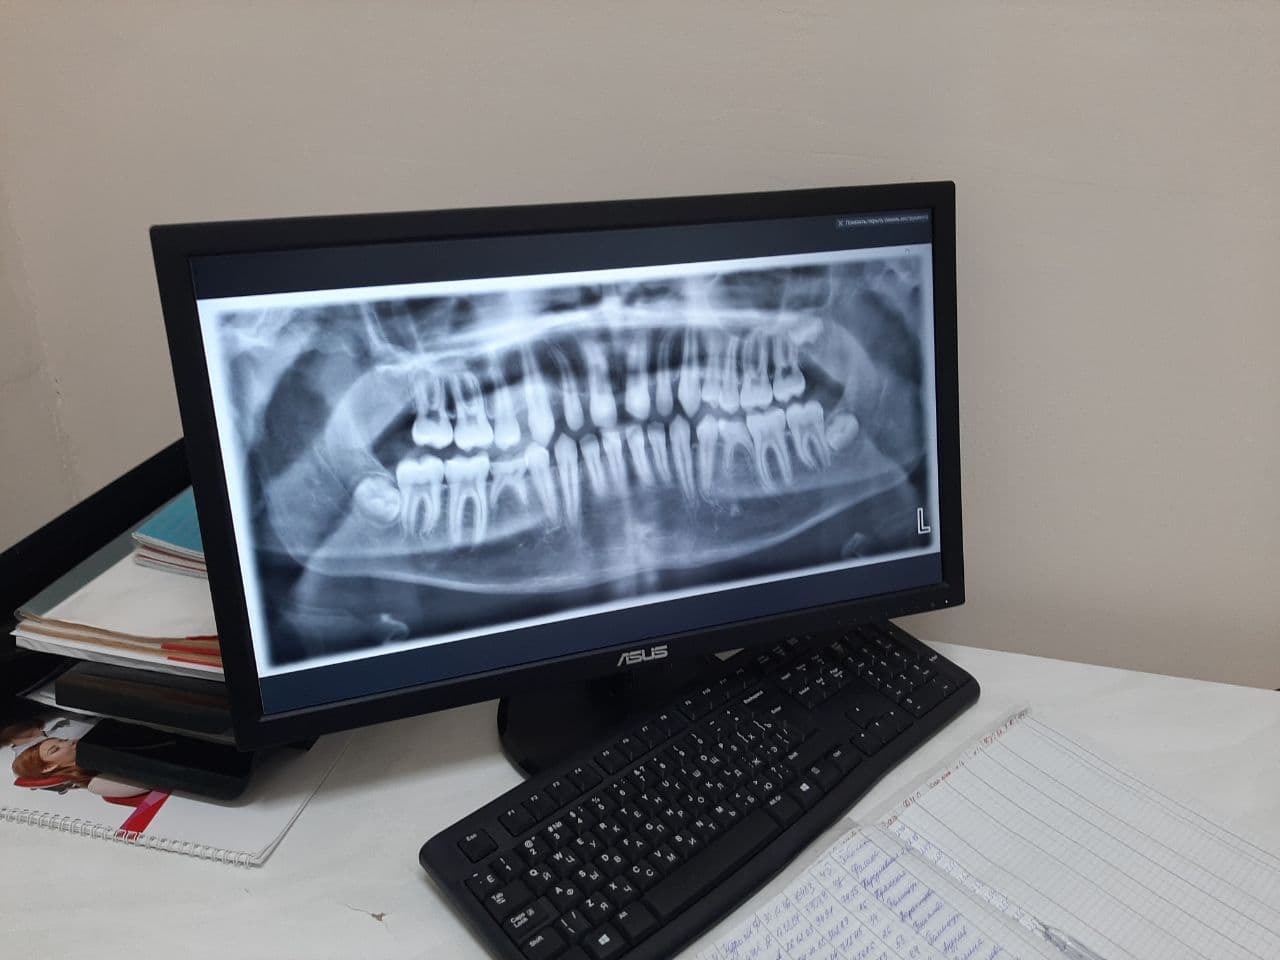

В детской стоматологической поликлинике Севастополя  на улице Ленина появился новый цифровой рентген-аппарат. Аппаратура, закупленная по поручению директора Департамента здравоохранения, позволяет делать детям панорамные снимки зубов, необходимые для ортодонтического лечения. Об этом сообщил главный врач медицинского учреждения Вячеслав Никольский.

«Аппарат позволяет в цифровом режиме, без использования пленки, без лучевой нагрузки на пациента, увидеть всю картину в полости рта: и молочные зубы, и постоянные зубы, и зачатки зубов. Можно посмотреть, нормально ли развивается челюсть, изучить строение костной ткани, суставов. Исходя из этого, ортодонт может составить правильный план лечения и обеспечить, чтобы зубы маленького пациента развивались ровно и красиво. Мы эту диагностику стали проводить впервые  и во всех наших филиалах: снимок, который делается в поликлинике на улице Ленина, могут увидеть в любой другой нашей стоматологии, и любой врач сразу может начинать с ним работать», - сообщил главный врач.

Стоимость аппарата превышает миллион рублей. Для всех пациентов детской  стоматологической поликлиники снимки делаются бесплатно. Это первый подобный аппарат в государственной стоматологической службе.